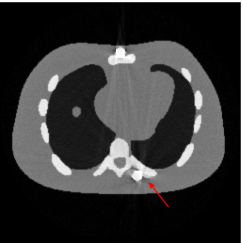

Figure 7(a) shows that the reconstructed NCAT phantom from FBP has severe metal artifacts and is noisy. The reconstructed image from the unweighted JSR model (3.2) shown in Figure 7(b) has a better visual effect with noticeably less noise and metal artifacts. Sharp edges are also well preserved except for the blurry effects in the region surrounding the metals. The reconstructed image from NMAR shown in Figure 7(c) also has most of the metal artifacts suppressed and the regions surrounding the metals are much less blurry than the unweighted JSR. However, the unweighted JSR does a better job than NMAR in suppressing noise and preserving sharp image features away from the metals. TV-FADM is able to reconstruct images with minimum metal artifacts and noise, as shown in Figure 7(d). However, the metal components are fused with nearby structures which is highlighted by the red arrow. The reconstructed image from proposed re-weighted JSR model has the best overall quality with rather minor metal artifacts.

Figure 8 shows the reconstructed cerebral phantom from different methods. We highlight some regions with more distinct differences with red contours. Since the cerebral phantom contains more textures, it is more challenging than the NCAT phantom. The pros and cons of these methods are mostly the same as the previous example. However, we note that the reconstructed image from TV-FADM shown in Figure 8(e) has severe artifact, which is due to the well-known staircase artifact of TV regularization. We found that TV-FADM is relatively sensitive to the choice of its parameters. It is not easy to balance between sharpness of image features and metal artifacts reduction. The soft tissue around metal components is also not well preserved by the NMAR method as indicated by the blue arrow in Figure 8(d). Furthermore, the circled areas in Figure 8(d) show that there are still some artifacts around the metal. Same as the NCAT phantom, the proposed re-weighted JSR model has the best overall performance. Notice that the intensity of metals in Figure 8(d) and 8(f) seems lower than the rest of the reconstructed images. This is because we set the intensity of the metal components in the segmentation with the same mean value as that of bones. Increasing the value of metal components of can increase the intensity of metals in the reconstructed images, whereas it also introduces more artifacts around the metals.